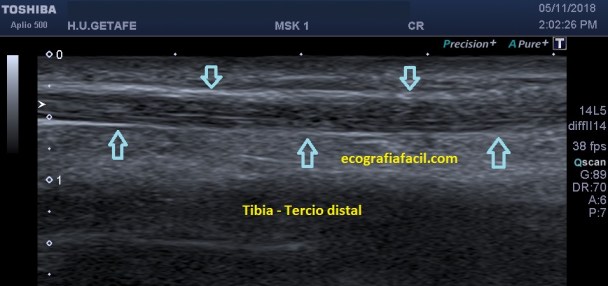

El tendón va muy pegadito a la tibia en este tramo distal de la tibia, buscando el maleolo, donde gira para ir a buscar su inserción en la cara interna del pie.

Es hiperecogénico, homogéneo, grande y estriba la dificultad de estudio cuando bordea el maleolo interno del tobillo, ahí necesitaremos mucha técnica.

Tendón Tibial Posterior: Este tendón se estudia desde el tercio medio y distal de la tibia por su cara interna y posterior justo detrás de la Tibia, es el que va pegado a ella, pero muy cerca de él está el Flexor de los Dedos que nos puede llevar a equívoco en la exploración, la clave es saber situarlos, el que nos interesa es el que va pegado a la Tibia.